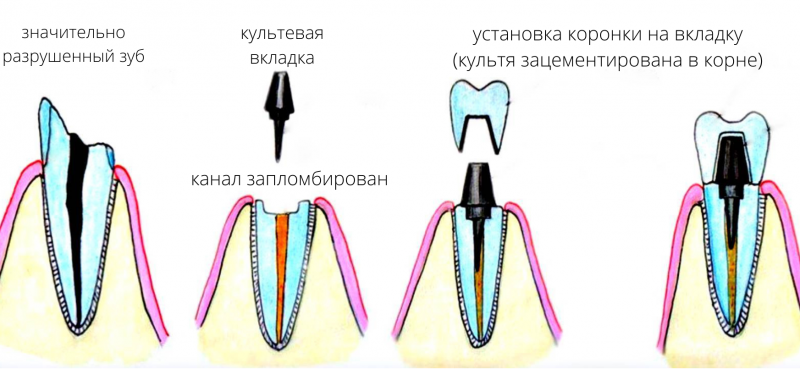

Циркониевые коронки и штифты: современные решения в стоматологии

Раздел: Необычные решения